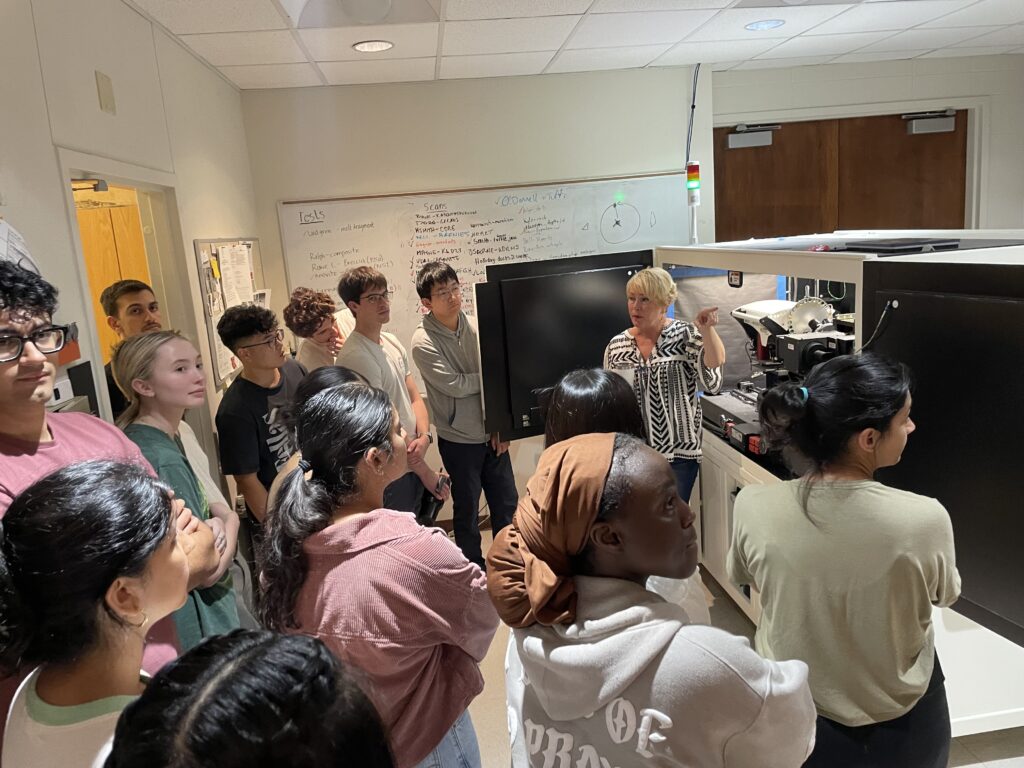

Pedagogy

Dr. Bush uses a problem and project-based approach to promote an active learning classroom. Classes combine fundamental concepts in medicine, physiology, physics and engineering with real world examples and uses of medical imaging.